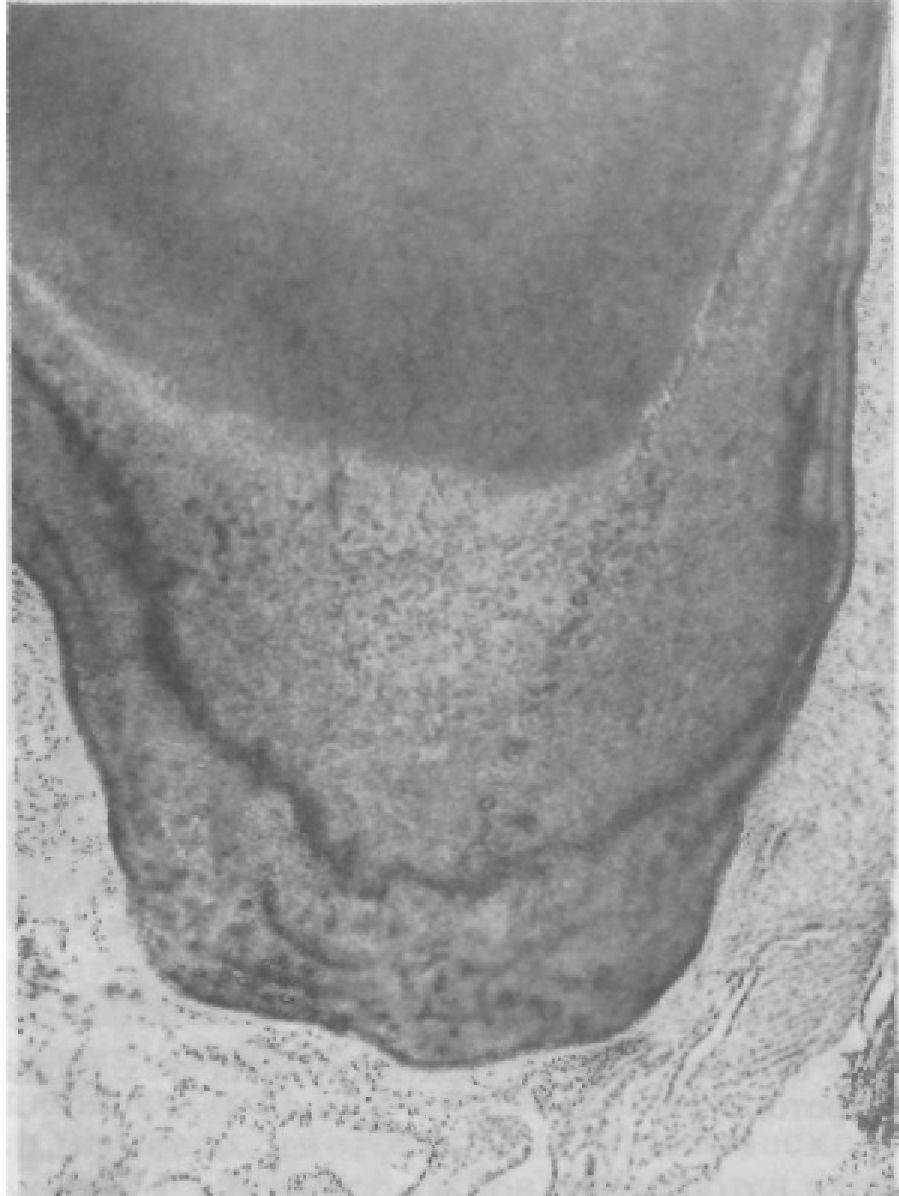

В пульпе патологически стертых зубов имеются существенные изменения (рис. 85). Они выражаются, в частности, в следующем:.

♦ В изменении васкуляризации: обеднение пульпы сосудами, склерозирование сосудов; иногда, наоборот, отмечаются усиленная васкуляризация, небольшие очаги кровоизлияний;.

в частичной или полной вакуолизации, атрофии одонтобластов, уменьшении числа клеточных элементов; в сетчатой атрофии, склерозе, гиалинозе пульпы.

Рис. 85. Вакуолизация слоя одонтопластов при патологической стертости. Микрофото.

Выраженность поражения пульпы зависит от степени патологической стираемости зубов. В нервном аппарате пульпы отмечаются изменения типа раздражения: гипераргирофилия, утолщение осевых цилиндров.